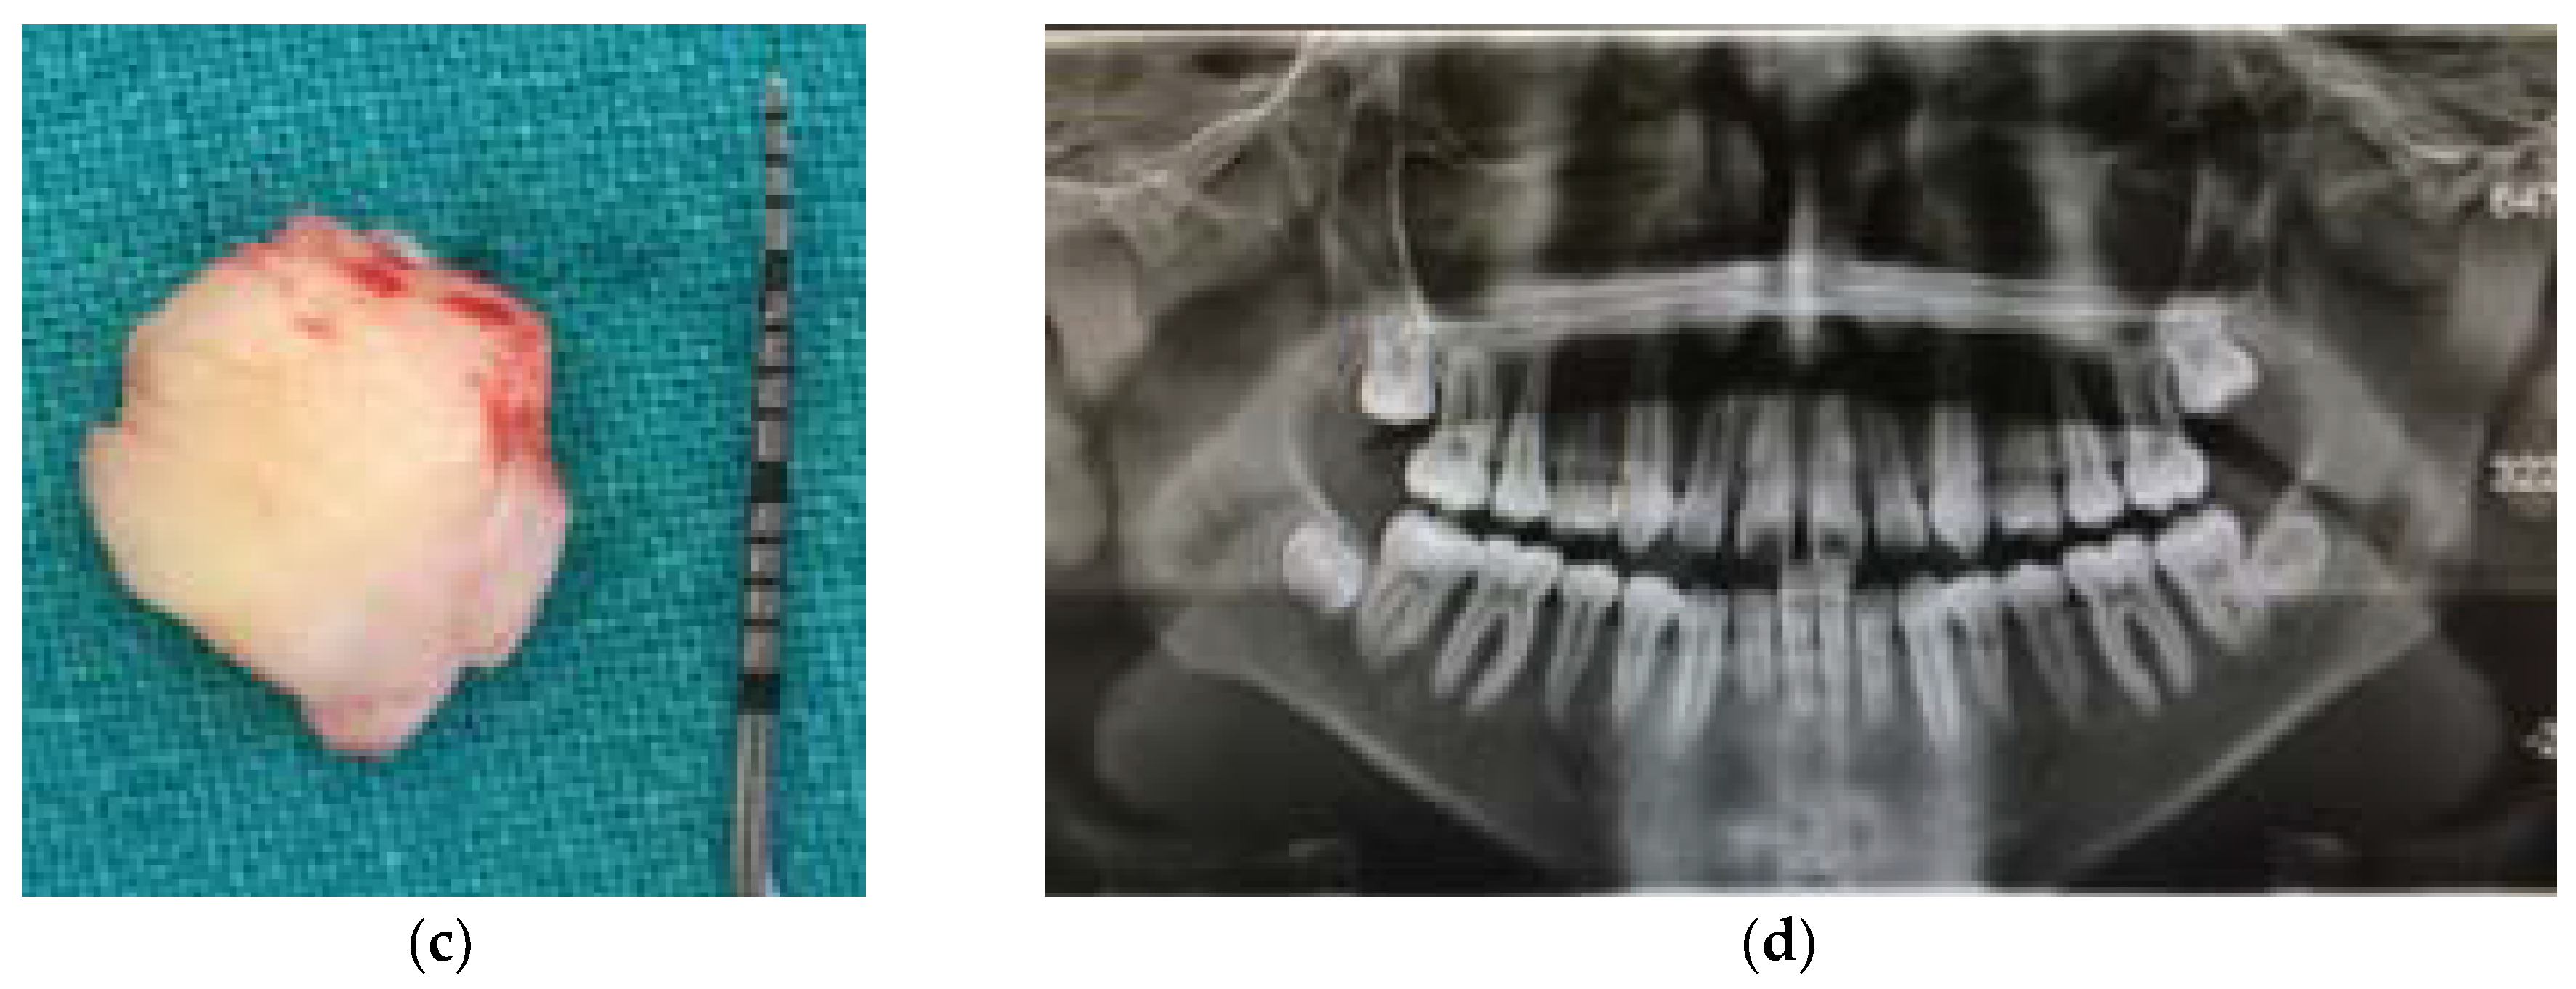

In the first group, patients underwent surgical removal of the mucosa (operculectomy) covering retained teeth. The area was treated with 2% lignocaine hydrochloride solution with adrenaline (1:80,000). Patients received no antibiotics prior to the surgery. Local antimicrobial prophylaxis was performed by rinsing with 0.2% chlorhexidine gluconate before surgical excision. The surgical excision of the flap of gum overlying second molars (Figure 1a–c) was performed with a surgical scalpel blade No 10. The control group consisted of patients whose parents refused to perform operculectomy. They were not treated but only followed for 12 months. Outcomes after treatment and outcomes without treatment were evaluated. Treatment outcome was considered successful if spontaneous eruption occurred within 1 year after surgical uncovering. Occlusion was considered successful if the tooth erupted vertically and the occlusal surface of the retained tooth was 2 mm or less from the occlusal plane.

Figure 1.

Example of a case treated with operculectomy. (a) Pre-surgical occlusal vision; (b) post-surgical occlusal vision; (c) example of the amount of soft tissue being removed in each side; (d) example of pre-treatment orthopantomography.